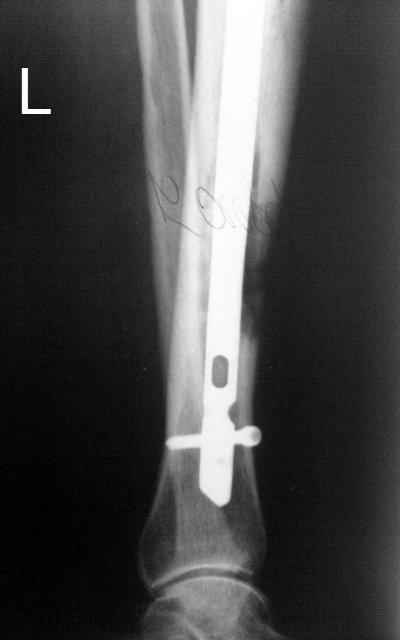

Итак, в настоящий момент больной пришел к нам с полной нагрузкой на оперированную конечность и с такой картиной (см. приложение). Участок мягких тканей с передней стенкой нижней трети ББК, выгнил и представляет дефект 2×2,5 см. На перевязке - циркулярный(?) некроз костной трубки.

Пациенту за 70 лет. Мои соображения: 1 этап - резекция tibia + косая остеотомия fibula + «острое» укорочение + IM цемент-гвоздь с а/б + beads. 2 этап (по заживлению раны) – удаление цемент-гвоздя + (LATN) Lengthening and Then Nailing. Прошу помощи по тактике.Никита Заднепровский

Сегментарного некроза не видно. Есть только краевой дефект спереди, задняя стенка вполне хорошая, и со стержнем есть условия для ее утолщения со временем. Так что проблему должна решить местная санация (если доступно, использовать VAC). Если грануляции не закроют все, что надо закрыть, придется делать пластику полнослойным лоскутом. Идеально бы - с микроососудистым анастомозом.

Позволю высказать свое мнение. У меня есть сомнения, что задняя стенка большеберцовой кости осталась "здоровой". Если после первой операции костная ткань и могла остаться частично жизнеспособной, то развившаяся гнойная инфекция наверняка способствовала окончательному некрозу кости.

Я бы, наверное, после удаления штифта сосредоточился на определения жизнеспособности кости по задней поверхности. Если будут сомнения, то я бы сделал резекцию.

Тогда можно рассмотреть вопрос одновременного удаления штифта, мышечной (в данной области применим проксимально отсеченный лоскут камбаловидной мышцы) или микрохирургической (что более надежно) пластики дефекта мягких тканей, остеотомии проксимального фрагмента большеберцовой кости, остеосинтеза блокируемым штифтом с а/б покрытием, наложения простого аппарата Илизарова (можно из полуколец) для дистракции на штифте. При данном варианте пациент сохраняет возможность полной опоры на ногу, что очень важно для заживления у пожилого пациента) и отпадает необходимость в проведении дополнительный операций (при благоприятном развитии событий).

Выкладываю картинки похожей пациентки. Извините, что без окончательных снимков (сейчас их нет под рукой). Правда мы имели проблемы у данной больной после снятия аппарата, когда промежуточный фрагмент большеберцовой кости сместился на 1,5 см дистально и отошел от проксимальной части кости. До сих пор у пациентки на снимках определяется лишь тонкая полоска кости по задней поверхности за штифтом (образовалось что-то вроде маленького регенерата)в области стыковки промежуточного и проксимального фрагментов. Больная пока решила подождать. Не хочет оперироваться, так как ходит не хромая, работает.